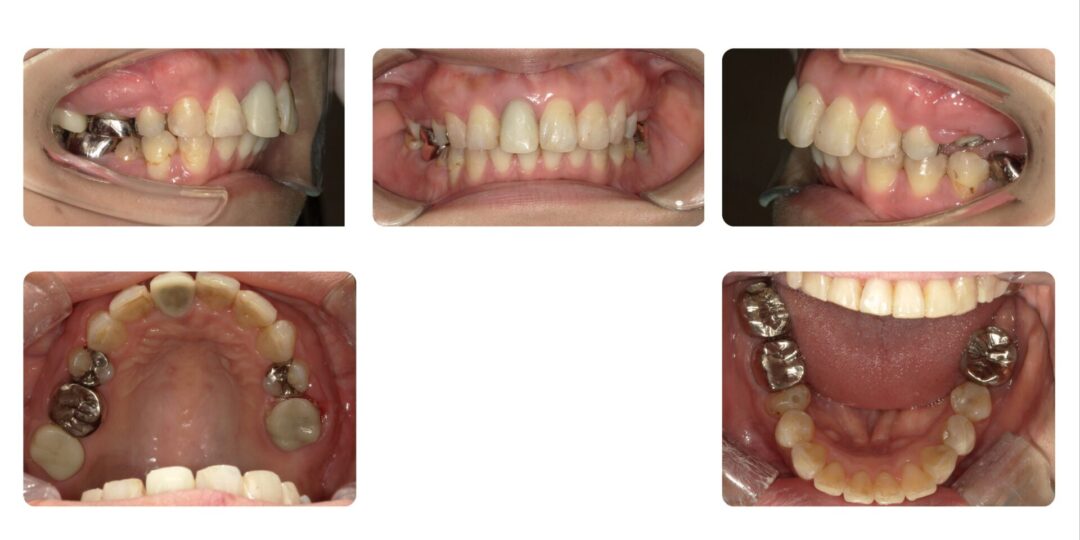

矯正治療後

成人歯科矯正 非抜歯 マルチブラケット装置

1年11ヶ月